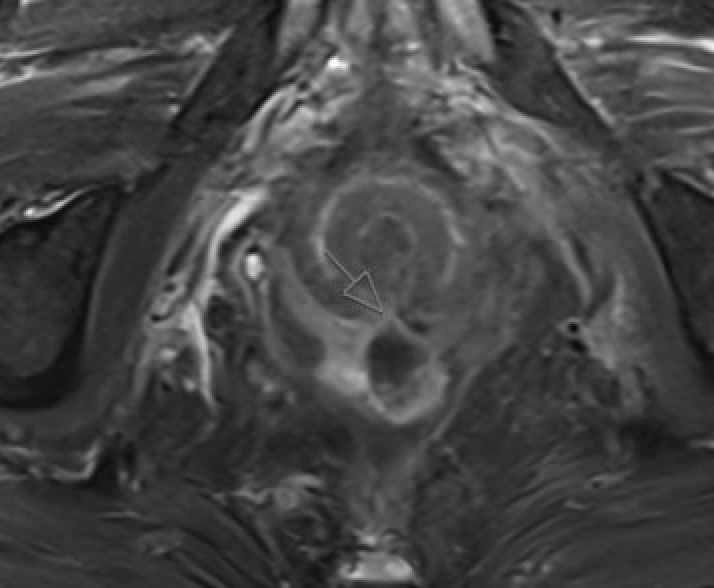

Perianal fistula Small-FOV T2W FSE along anal canal is key. Report: tract type (Parks classification — intersphincteric / transsphincteric / suprasphincteric / extrasphincteric), internal and external openings, branches, abscess. DWI + post-Gd for abscess vs granulation vs fibrosis

Small-FOV T2W MRI showing perianal fistula tract with internal opening at dentate line

Perianal fistula: T2W tract, internal opening, sphincter relation